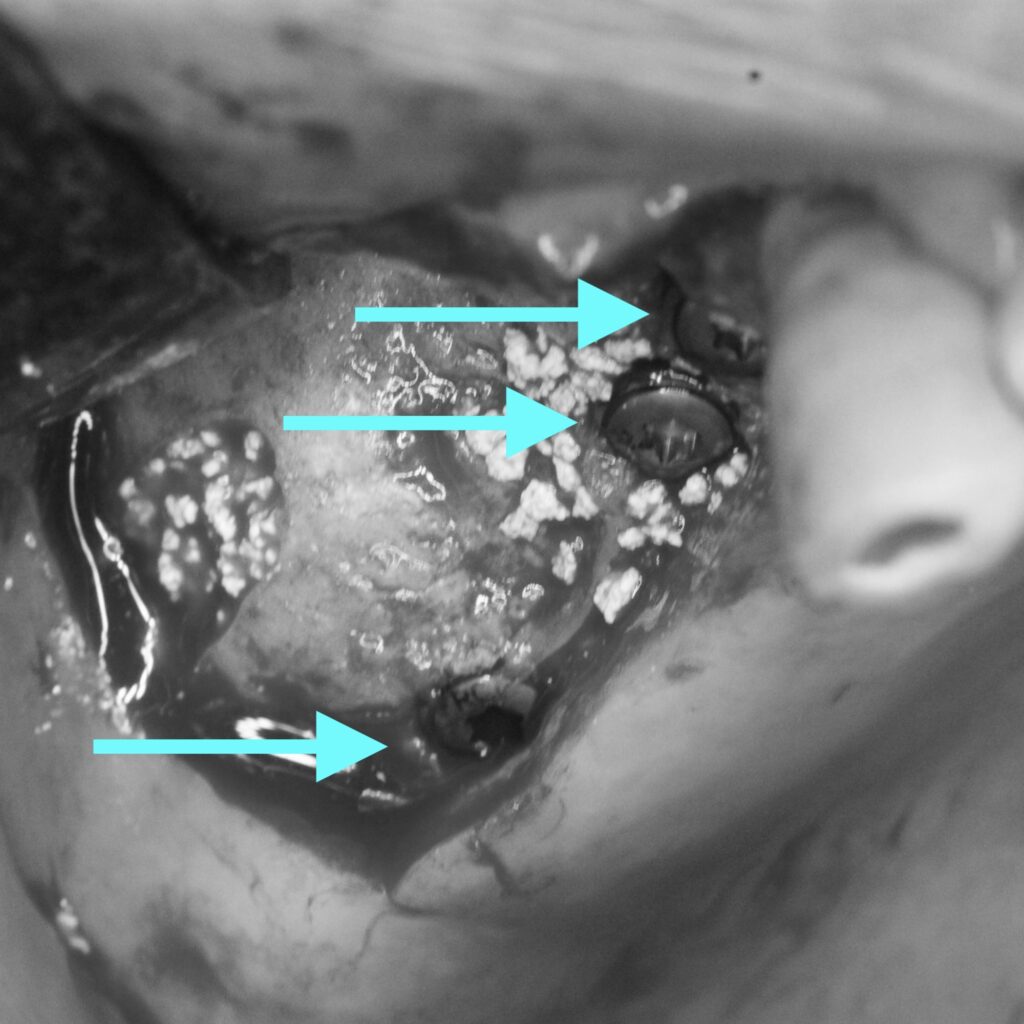

実際の処置後です。

下の歯と本数を揃えるため、計画を再立案し3本のインプラントを埋入しました。

インプラントの上にドーム状に広がっているのがサイナスリフトを行い填入された人工骨です。

予定通りの場所に、予定通りの方法でインプラント手術を終えることができました。